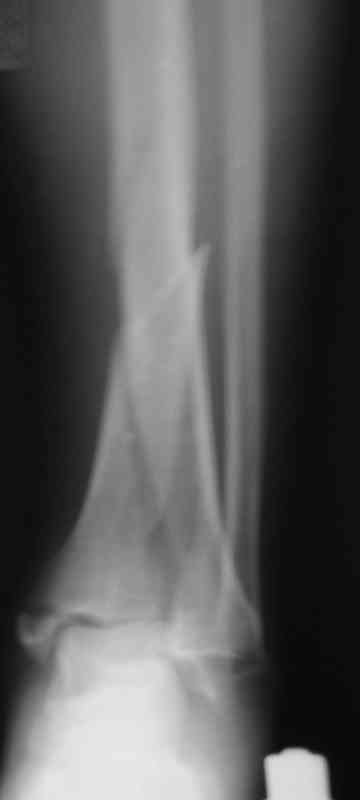

Фото с операции

Сегодня прооперировали. Длительность 4-50. Начали как и говорил сверху вниз линейным разрезом - фиксация задне-латерального отломка к проксимальному 2мя винтами, затем "прилепили" к ним передне-медиальный (пришлось повозиться - была интерпозиция и довольно "сложный" винт) - к проксимальному 1 винтом и к задне-латеральному 1 винтом.Кстати на фото видно - у передне-медиального отломка еще осколок в области сустава, несколько смят. Далее началось веселье - второй доступ - задне-наружный к латеральной лодыжке и заднему краю, но оказалось, что задний край больше задне-медиальный (по снимкам было непонятно). Плюс к этому репозиция его мягко говоря сложновата (больной на спине, стол низкий и не поднимается). В общем выставили, фискировали 2мя винтами, на ЭОПе вроде стал, только верх отошел. Латеральную лодыжку заведующий решил интрамедуллярно (не хотел еще винты толкать), сначала 3мм спицей - нестабильно, затем 4мм стержень (не помню по автору) - ОК (кстати в месте перелома мелкая крошка - дефект до 5х7 мм по кортикалу). Ну медиальная лодыжка стандартно - третий разрез - винт 3,5 мм. Визуально все стабильно. На Р-контроле - видна небольшая ступенька заднего края по одному из контуров.

> к проксимальному 1 винтом и к задне-латеральному 1 винтом. Кстати на

> фото видно - у передне-медиального отломка еще осколок в области

А можно посмотреть этапные фото в ходе операции?

> сустава, несколько смят. Далее началось веселье - второй доступ -

> задне-наружный к латеральной лодыжке и заднему краю, но оказалось, что

> задний край больше задне-медиальный (по снимкам было непонятно).

По снимкам до операции задний край находился в правильных взаимоотношениях к передне-медиальной части суставного конца tibia, то есть мог быть фиксирован закрыто спицами или винтом.